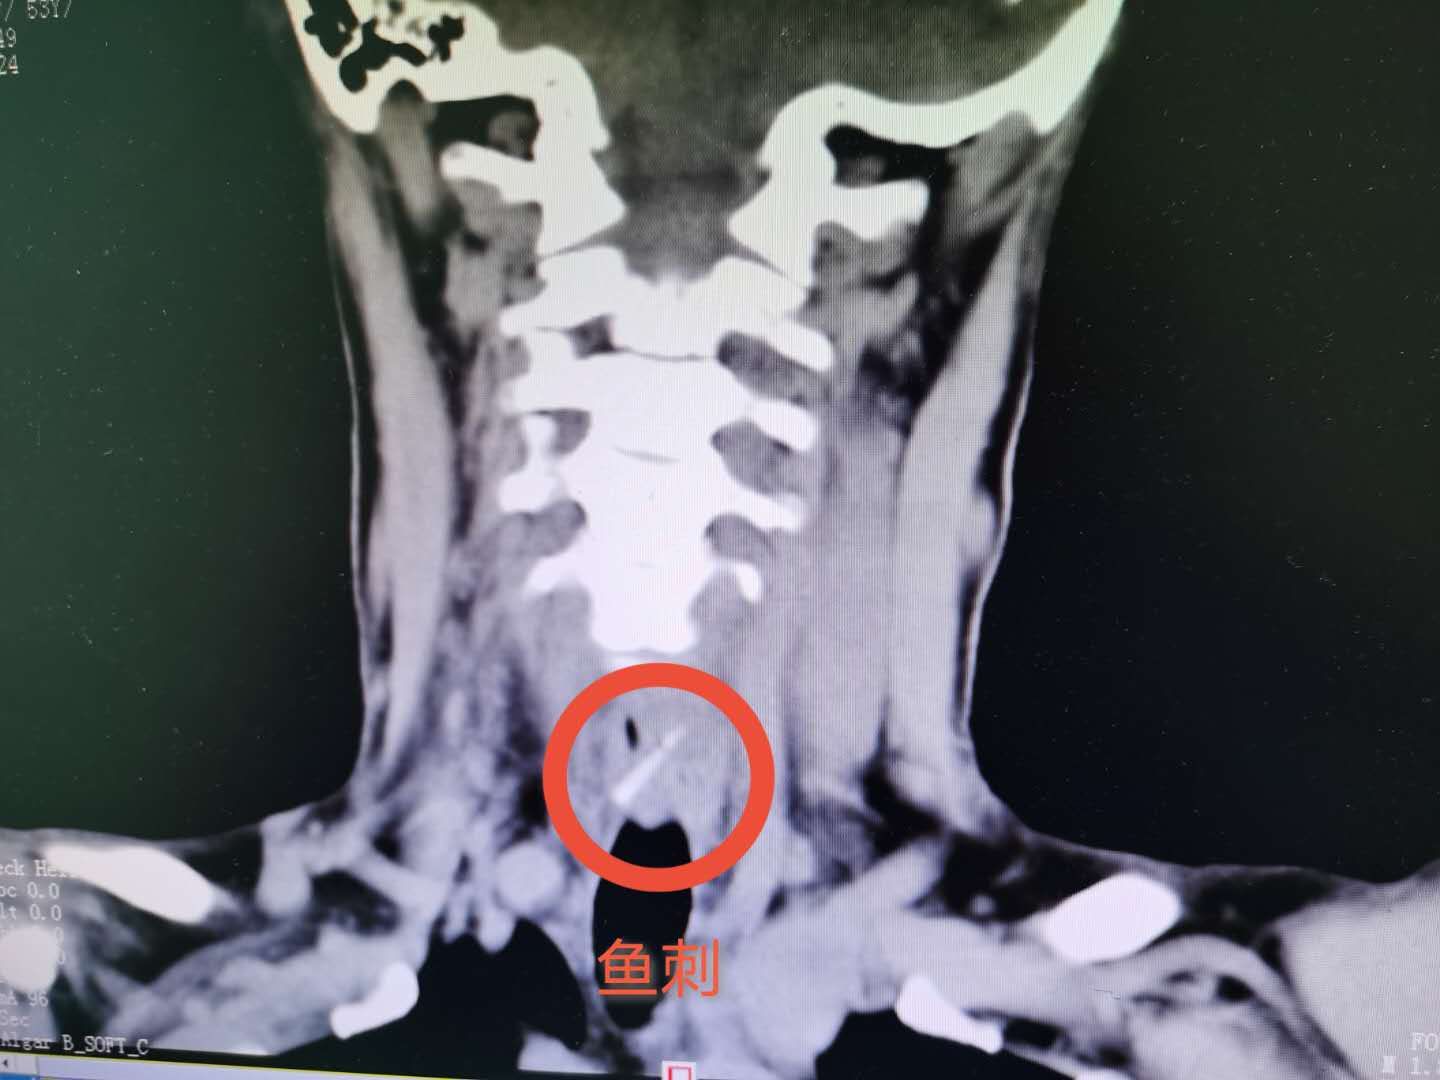

据接诊的李乐章副主任医师介绍,当时汤女士来医院就诊时,通过喉镜及颈段食道CT检查诊断发现,她的食管可以看到鱼刺而且出现穿孔情况,立即予以急诊全麻下行食道镜下食道异物取出术,在食道内取出一约1.5cm的鱼刺,术中还发现有根鱼刺穿破食道进入颈部皮肤表层,再次行颈侧切开食管异物取出术,最后,成功将鱼刺取出。术中可以见到鱼刺已经穿过食道,并且到达食道侧的后壁,稍有不慎将会刺破大血管,随时都有大出血危及生命可能,所幸救治及时,目前,汤女士颈部伤口愈合可,能够自主进食。